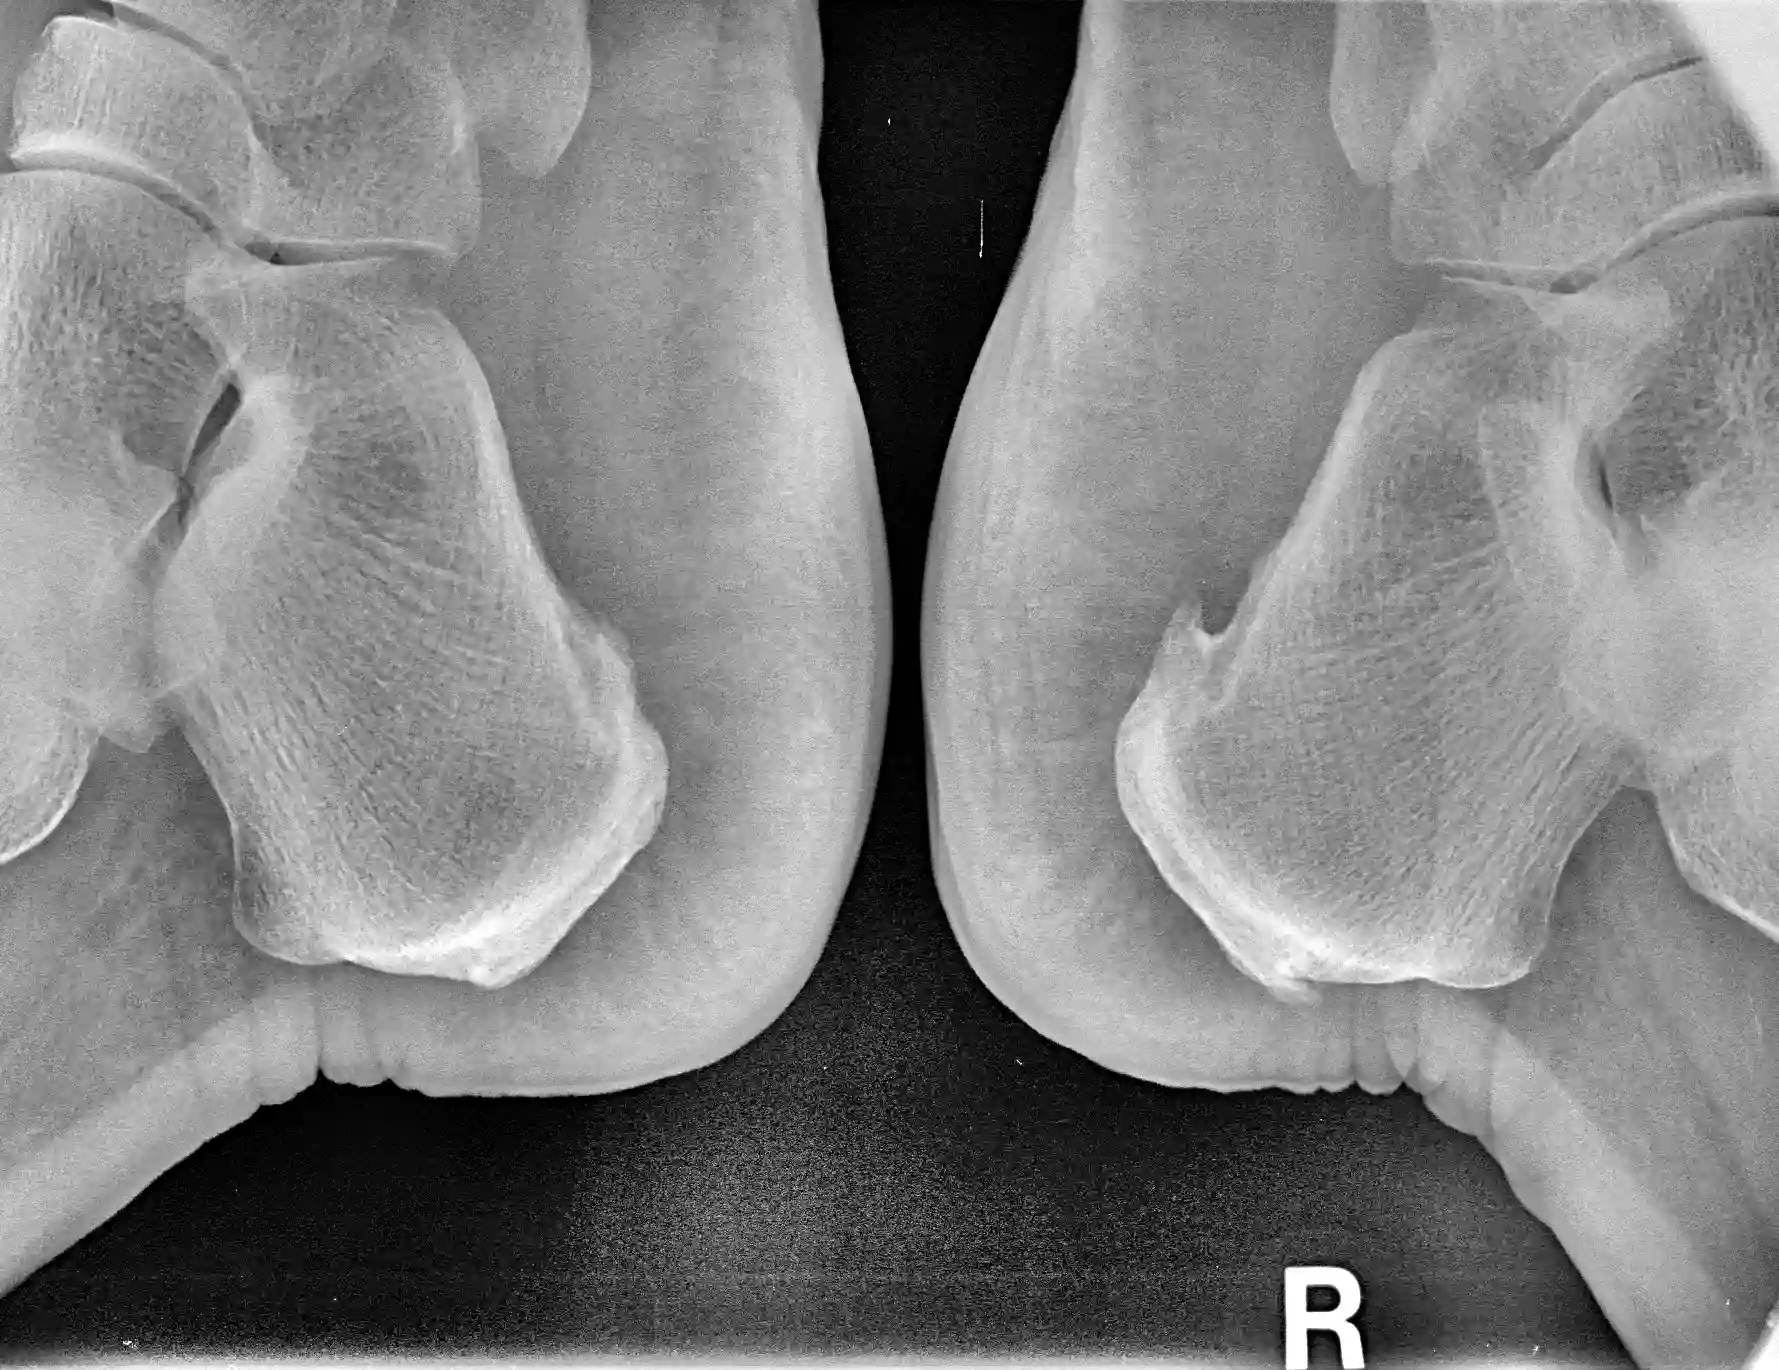

Radiología digital

Contamos con radiología digital para diagnosticar fracturas, desviaciones óseas y otras alteraciones estructurales del pie de manera rápida y con mínima exposición a radiación.